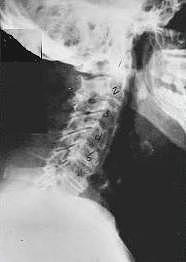

Phase One Subluxation Degeneration is seen in subluxations that have been present for up to twenty years. This phase is characterized with a loss or change in the normal curve in the spine. On this example you can see that the normal forward (lordotic) curve is lost. This spine even has developed a reverse curve in the neck. The disc spaces have also begun to exhibit a slight change in shape. One good point is that the bodies of each of the vertebrae (the square part in front) still exhibits clean clear borders. Segmental motion may be abnormal but overall motion is probably not affected. Chiropractic reconstructive care for a phase one can take from 6 to 18 months. More than 80% of people with Phase One Subluxation Degeneration have no pain. Therefore, if left uncorrected, phase one continues to progress with time until it eventually reaches the next phase.

Phase two subluxation degeneration is normally seen in subluxations that have been present between 20 and 40 years. This phase has some of the same characteristics of the previous phase including a loss of normal curvature and position as well as an alteration in segmental motion. In addition, spines with Phase Two Subluxation Degeneration many times show a reduction in the patient's range of motion in that area. X-rays of a phase two begin to show calcium changes or buildup at certain levels of the spine. These changes are sometimes called by many names including spurs and arthritis. Disc spaces between the affected vertebrae are noticeably narrower and may appear to be flattening out. Although most people with Phase Two Subluxation Degeneration may not exhibit any symptoms, some may start to feel stiff or achy. Chiropractic reconstructive care for patients in phase two ranges from 1.5 years to 2.5 years. Again, if Phase Two Subluxation Degeneration is left uncorrected it slowly advances to the next phase.